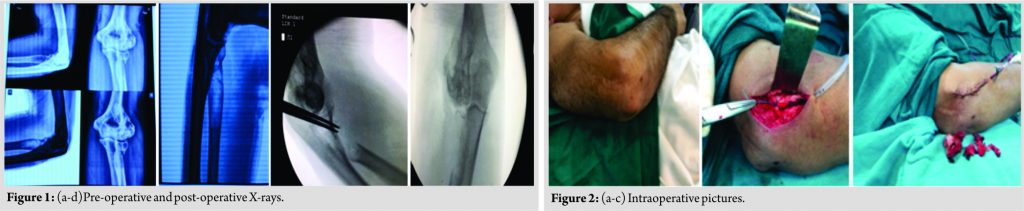

A 40-year-oldmale presented with the complaint of pain swelling over the right elbow but no fever for the past 10 days with a history of trauma 15 days back. In the past, a history of tuberculosis (TB) of elbow treated 10 years back on antituberculosis therapy, antituberculardrugs, and surgery synovectomy debridement of elbow joint through lateral approach later patient recovered well with satisfactory result. On physical examination, there was tenderness over lateral aspect of the elbow with restricted movement of elbow and wasting of forearm muscle. Swelling over elbow with no sign of inflammation or infection skin was normal. On investigation X-ray – pathological fracture of Radial head with eccentric ballooned expanded Radiolucency margin well circumscribed lesion Bone cyst (Fig. 1). MRI – mildly expansile lesion at proximally epiphysis-metaphysis adjacent to diaphyseal location of radius extending upto sub articular location abutting articular cartilage. Surgery was planned; the aim was to excise diseased part and get good functional recovery wide excision of tumor through anterolateral approach with injection of phenol (Fig. 2).

Tumor bone soft tissues send for biopsy including Radial head which was involved up to articular cartilages, (Fig. 3)Radial head reconstruction was not done because ABC extended from metaphysic – diaphysis junction to epiphysis cartilage of radial head. Post-operative recovery was satisfactory with good reasonable range of movement of the elbow (Fig. 4).